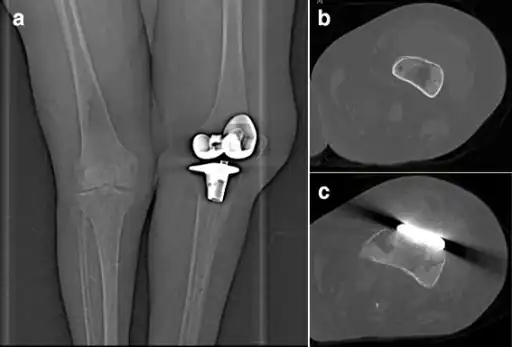

In humans, P. multocida is the most common cause of wound infections after dog or cat bites. The infection usually shows as soft tissue inflammation within 24 hours. High leukocyte and neutrophil counts are typically observed, leading to an inflammatory reaction at the infection site (generally a diffuse, localized cellulitis).[14] It can also infect other locales, such as the respiratory tract, and is known to cause regional lymphadenopathy (swelling of the lymph nodes). In more serious cases, a bacteremia can result, causing an osteomyelitis or endocarditis. Patients with a joint replacement (perhaps notably knee replacement) in place may, in particular, be at risk of secondary infection of that joint during an episode of P multocida cellulitis/bacteraemia. The bacteria may also cross the blood–brain barrier and cause meningitis.[7][15]